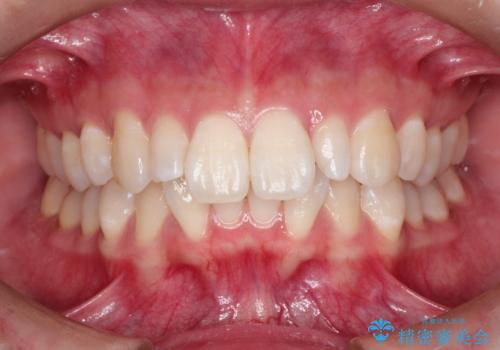

- 出っ歯と全体をきれいにしたいとのことで来院されました。

上顎の歯が全体的に前方に位置しているのと、前から2番目の歯が通常よりも小さい矮小歯という状態でした。

出っ歯をなおすために上顎の前から4番目の歯を抜歯して、引っ込めるのと、前から2番目の歯に通常の大きさのオールセラミックを装着して整った歯並びにすることにしました。

歯の大きさが通常と異なる場合は矯正治療で歯並びだけきれいにしても、整わないことがあります。

その場合はセラミックのかぶせ物を装着して歯の形を正常にすることで、さらに整った歯並びにすることができます。